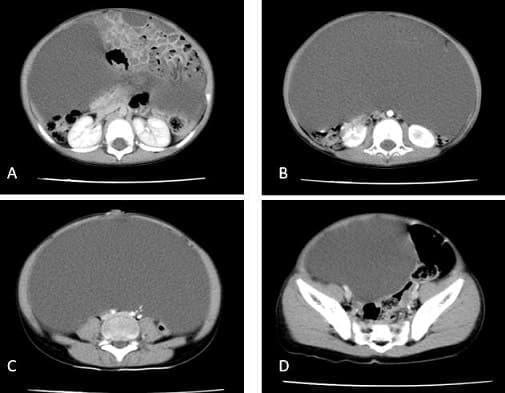

Se complementaron con una ecografía abdominal que reportó lesión quística ocupando casi la totalidad del abdomen, con una medida de al menos 121 x 120 mm y una tomografía de abdomen y pelvis contrastada que mostró una gran lesión quística dependiente del mesenterio, sobre la línea media, desde el epigastrio hasta el hipogastrio y hacia los lados extendiéndose por todo el hemiabdomen izquierdo y derecho, ocupando la totalidad de la cavidad abdominal, desplazando las asas intestinales lateralmente, hallazgos compatibles con quiste mesentérico (Figura 1).

Figura 1. Tomografía computarizada de abdomen contrastada. Se observa lesión

quística gigante con desplazamiento de asas intestinales. Las flechas señalan la lesión.

Fuente: los autores.